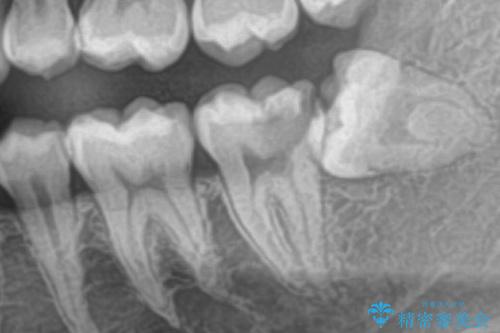

- 左下奥歯が痛いとの事で来院。

親知らずが炎症を起こしていたので抜歯をし、手前の歯は拡大鏡下で虫歯を取り除き、ジルコニアクラウンで治療をしました。